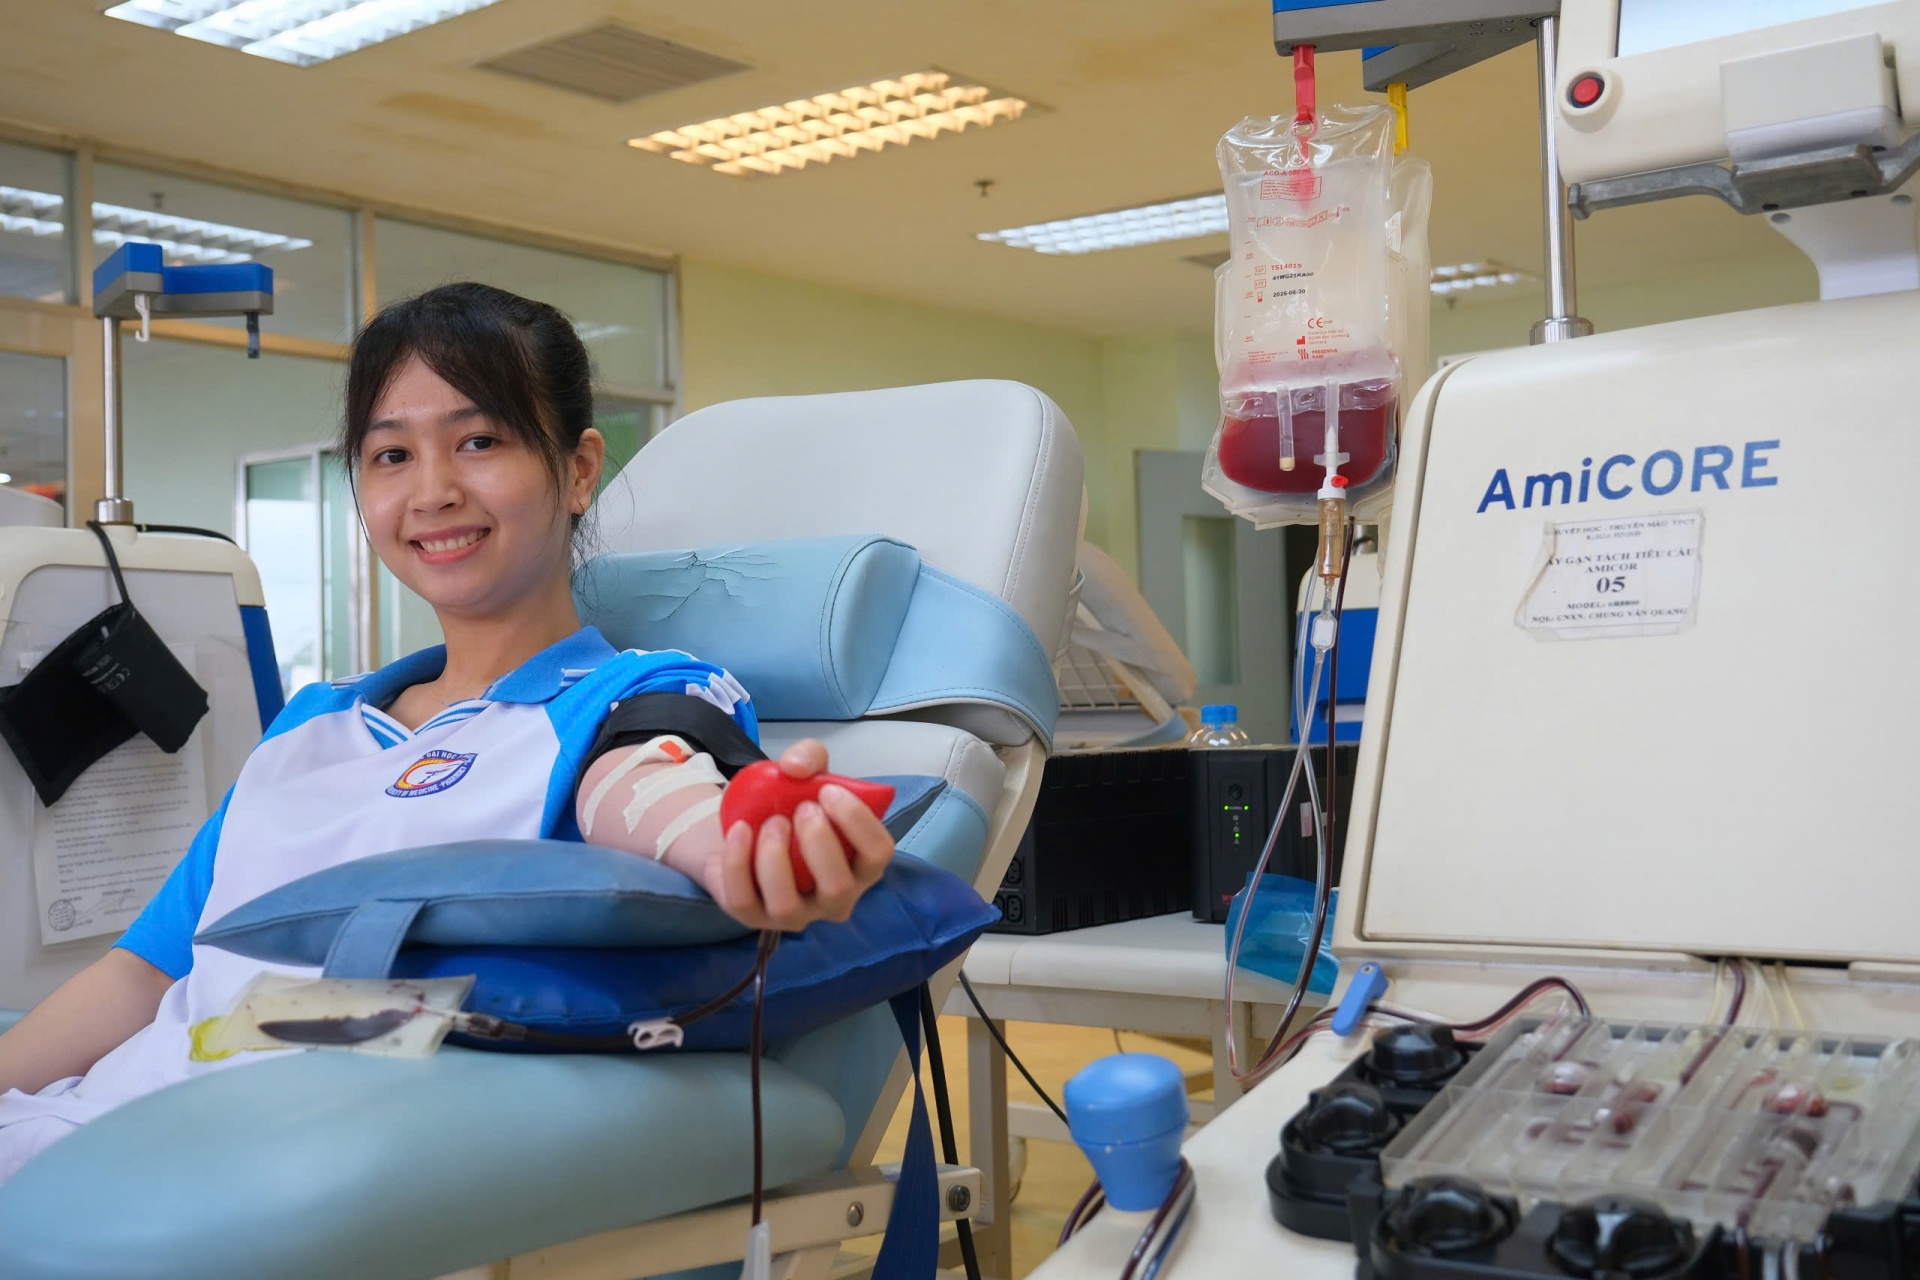

286 đơn vị máu từ chương trình hiến máu tình nguyện 2025 của Herbalife Việt Nam

Công an tỉnh Vĩnh Long hưởng ứng ngày hội hiến máu tình nguyện

Công an tỉnh Vĩnh Long hưởng ứng ngày hội hiến máu tình nguyện

Trách nhiệm và tự hào khi hiến máu cứu người